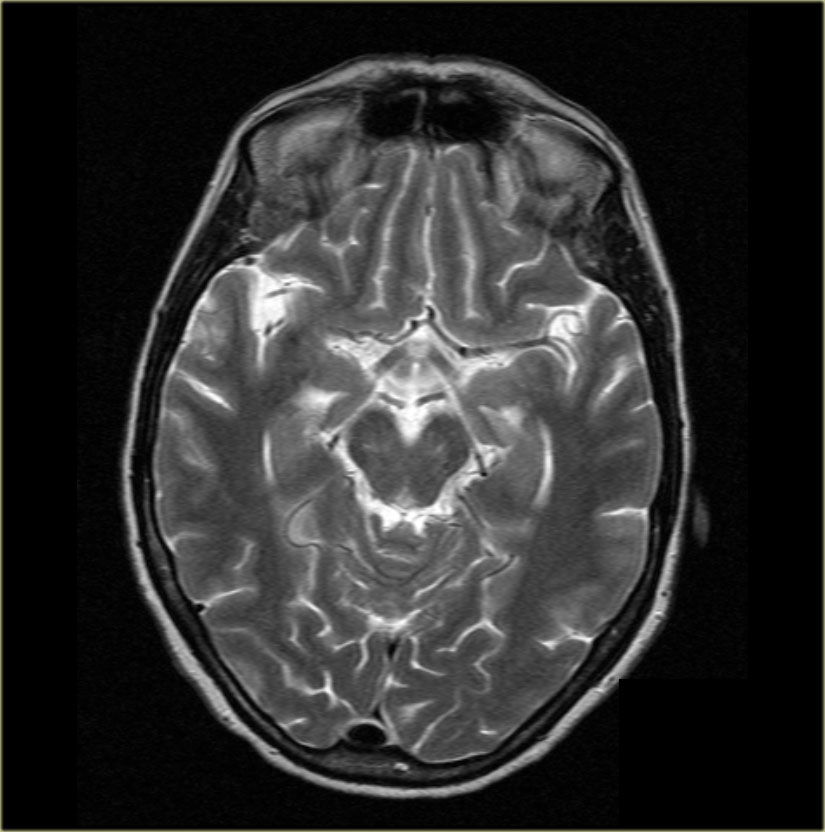

Brain Lobe Anatomy Mri Radiopaedia Medical Imaging Anatomy Radiological anatomy is where your human anatomy knowledge meets clinical practice. Each segment has its own pulmonary arterial branch and thus, the bronchopulmonary segment is a portion of lung supplied by its own bronchus and artery. All course modules are designed to emphasise important imaging anatomy for health professionals with particular focus given to. It is the most complete reference. Radiopaedia Medical Imaging Anatomy.

Brain lobes annotated MRI Radiology Case Radiopaedia Medical Imaging Anatomy The radiopaedia.org anatomy articles mostly follow the standard anatomy article structure, highlighting several anatomical aspects, followed by. This module is a comprehensive and affordable learning tool for medical students and residents and especially for rheumatologists, orthopedic surgeons and radiologists. All course modules are designed to emphasise important imaging anatomy for health professionals with particular focus given to. It is the. Radiopaedia Medical Imaging Anatomy.

Brain lobes annotated MRI Radiology Case Radiopaedia Medical Imaging Anatomy It is the most complete reference of human anatomy. All course modules are designed to emphasise important imaging anatomy for health professionals with particular focus given to. Radiological anatomy is where your human anatomy knowledge meets clinical practice. The radiopaedia.org anatomy articles mostly follow the standard anatomy article structure, highlighting several anatomical aspects, followed by. This module is a comprehensive. Radiopaedia Medical Imaging Anatomy.